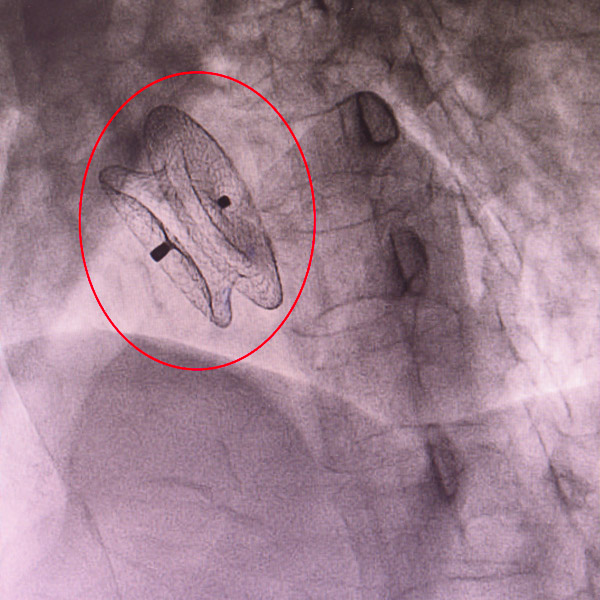

次日,手術開始,心血管內科結構性心臟病團隊在超聲團隊的全程引導下,為患者行房間隔缺損封堵術,利用導管將封堵傘準確置入下腔型房間隔缺損內并封堵成功,整個過程一氣呵成,僅花了20分鐘。心血管內科結構性心臟病團隊勇闖“禁區”的膽量除了來自于對先天性心臟病介入治療技術的嫻熟掌握,也離不開放射科、超聲科的全力配合,是MDT(多學科診療)成果的體現。

術后超聲顯示患者的心臟已恢復正常,僅僅留下了一顆針眼大小的傷口,兩日后便成功出院,患者及其家屬對醫護人員表達了衷心的感謝。